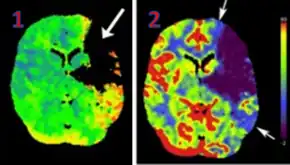

CT perfusion with flow and volume maps in cerebral infarction

Perfusion CT or CT Perfusion is a type of Perfusion Scanning using Computed Tomography. It is helpful in the evaluation of the vascularity of tissue in the body. In this, the temporal changes in tissue density are measured, providing information about the vascularity of the tissue. In CT perfusion, a contrast media injection is given, and then the scan is taken. The acquired data are post-processed to obtain perfusion maps with different parameters, such as BV (blood volume), BF (blood flow), MTT (mean transit time), and TTP (time to peak).[1][2]

CT Perfusion plays an important role in the assessment of Acute Ischemic Stroke. It is used to create maps of blood flow, blood volume, and mean transit time to assess the tissue and to differentiate between the core and penumbra in stroke.[3]